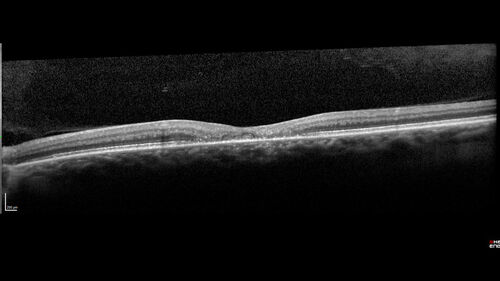

Macular Telangetasia MacTel - Nonproliferative

60 year old non-diabetic female with gradual vision loss for 20 years. VA 20/80 OD, 20/63 OS